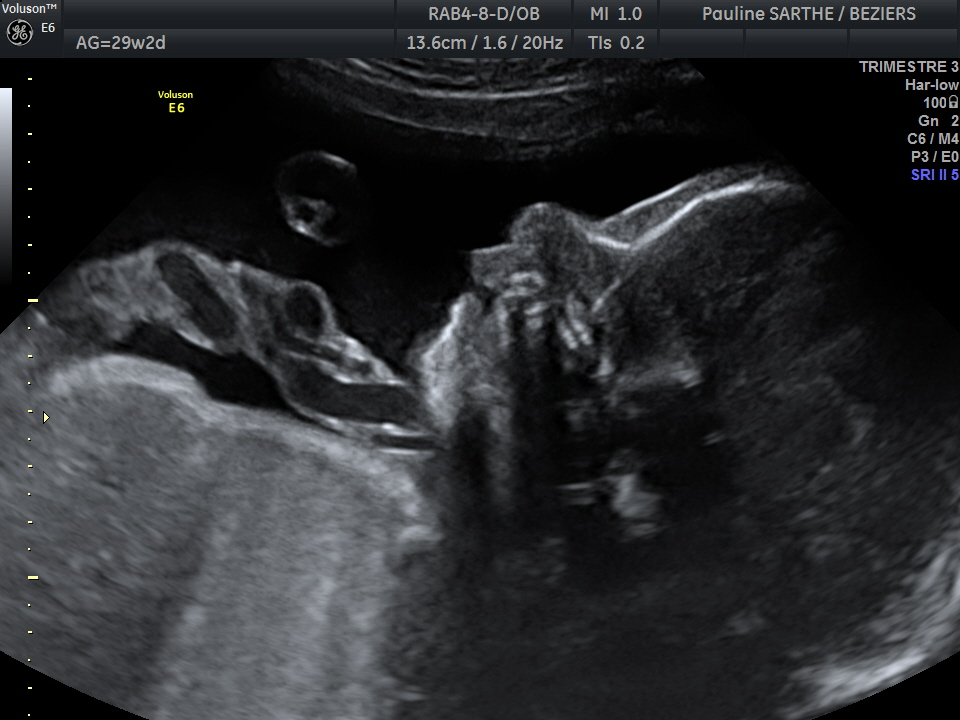

- l'échographie du 3 ème trimestre s'effectue de manière optimale entre 32 et 34 semaines d'aménorrhées.

Elle est importante pour s'assurer de la bonne croissance, de l'aspect des organes, de la position de votre bébé et du placenta à l'entrée dans le dernier trimestre.